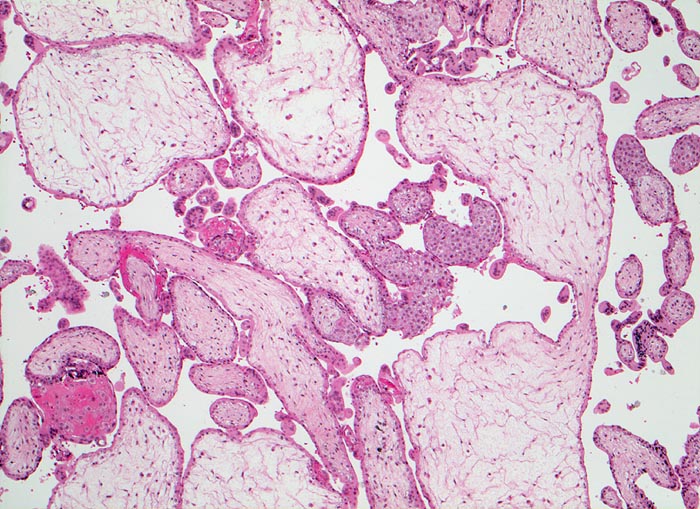

Windmole bei Trisomie 7

Gestörte Zottenverzweigungen. Mangelhafte Vaskularisation und hydropische Umwandlung des Stromas der Plazentarzotten. Trophoblast über weite Strecken einreihig und abgeflacht.

Zytogenetisch 47, XY, +7

32 jährige mit missed abortion in der 11. SSW

Morphologisch deskriptiv: Windmole. Mit 50% machen die Trisomien die häufigste Gruppe der Chromosomenaberrationen aus. Einige führen zum Frühabort (Trisomie 16, 7). Die Zotten zeigen mehr oder weniger herdförmige Entwicklungsstörungen, die den Verdacht auf eine Chromosomenaberration erlauben.